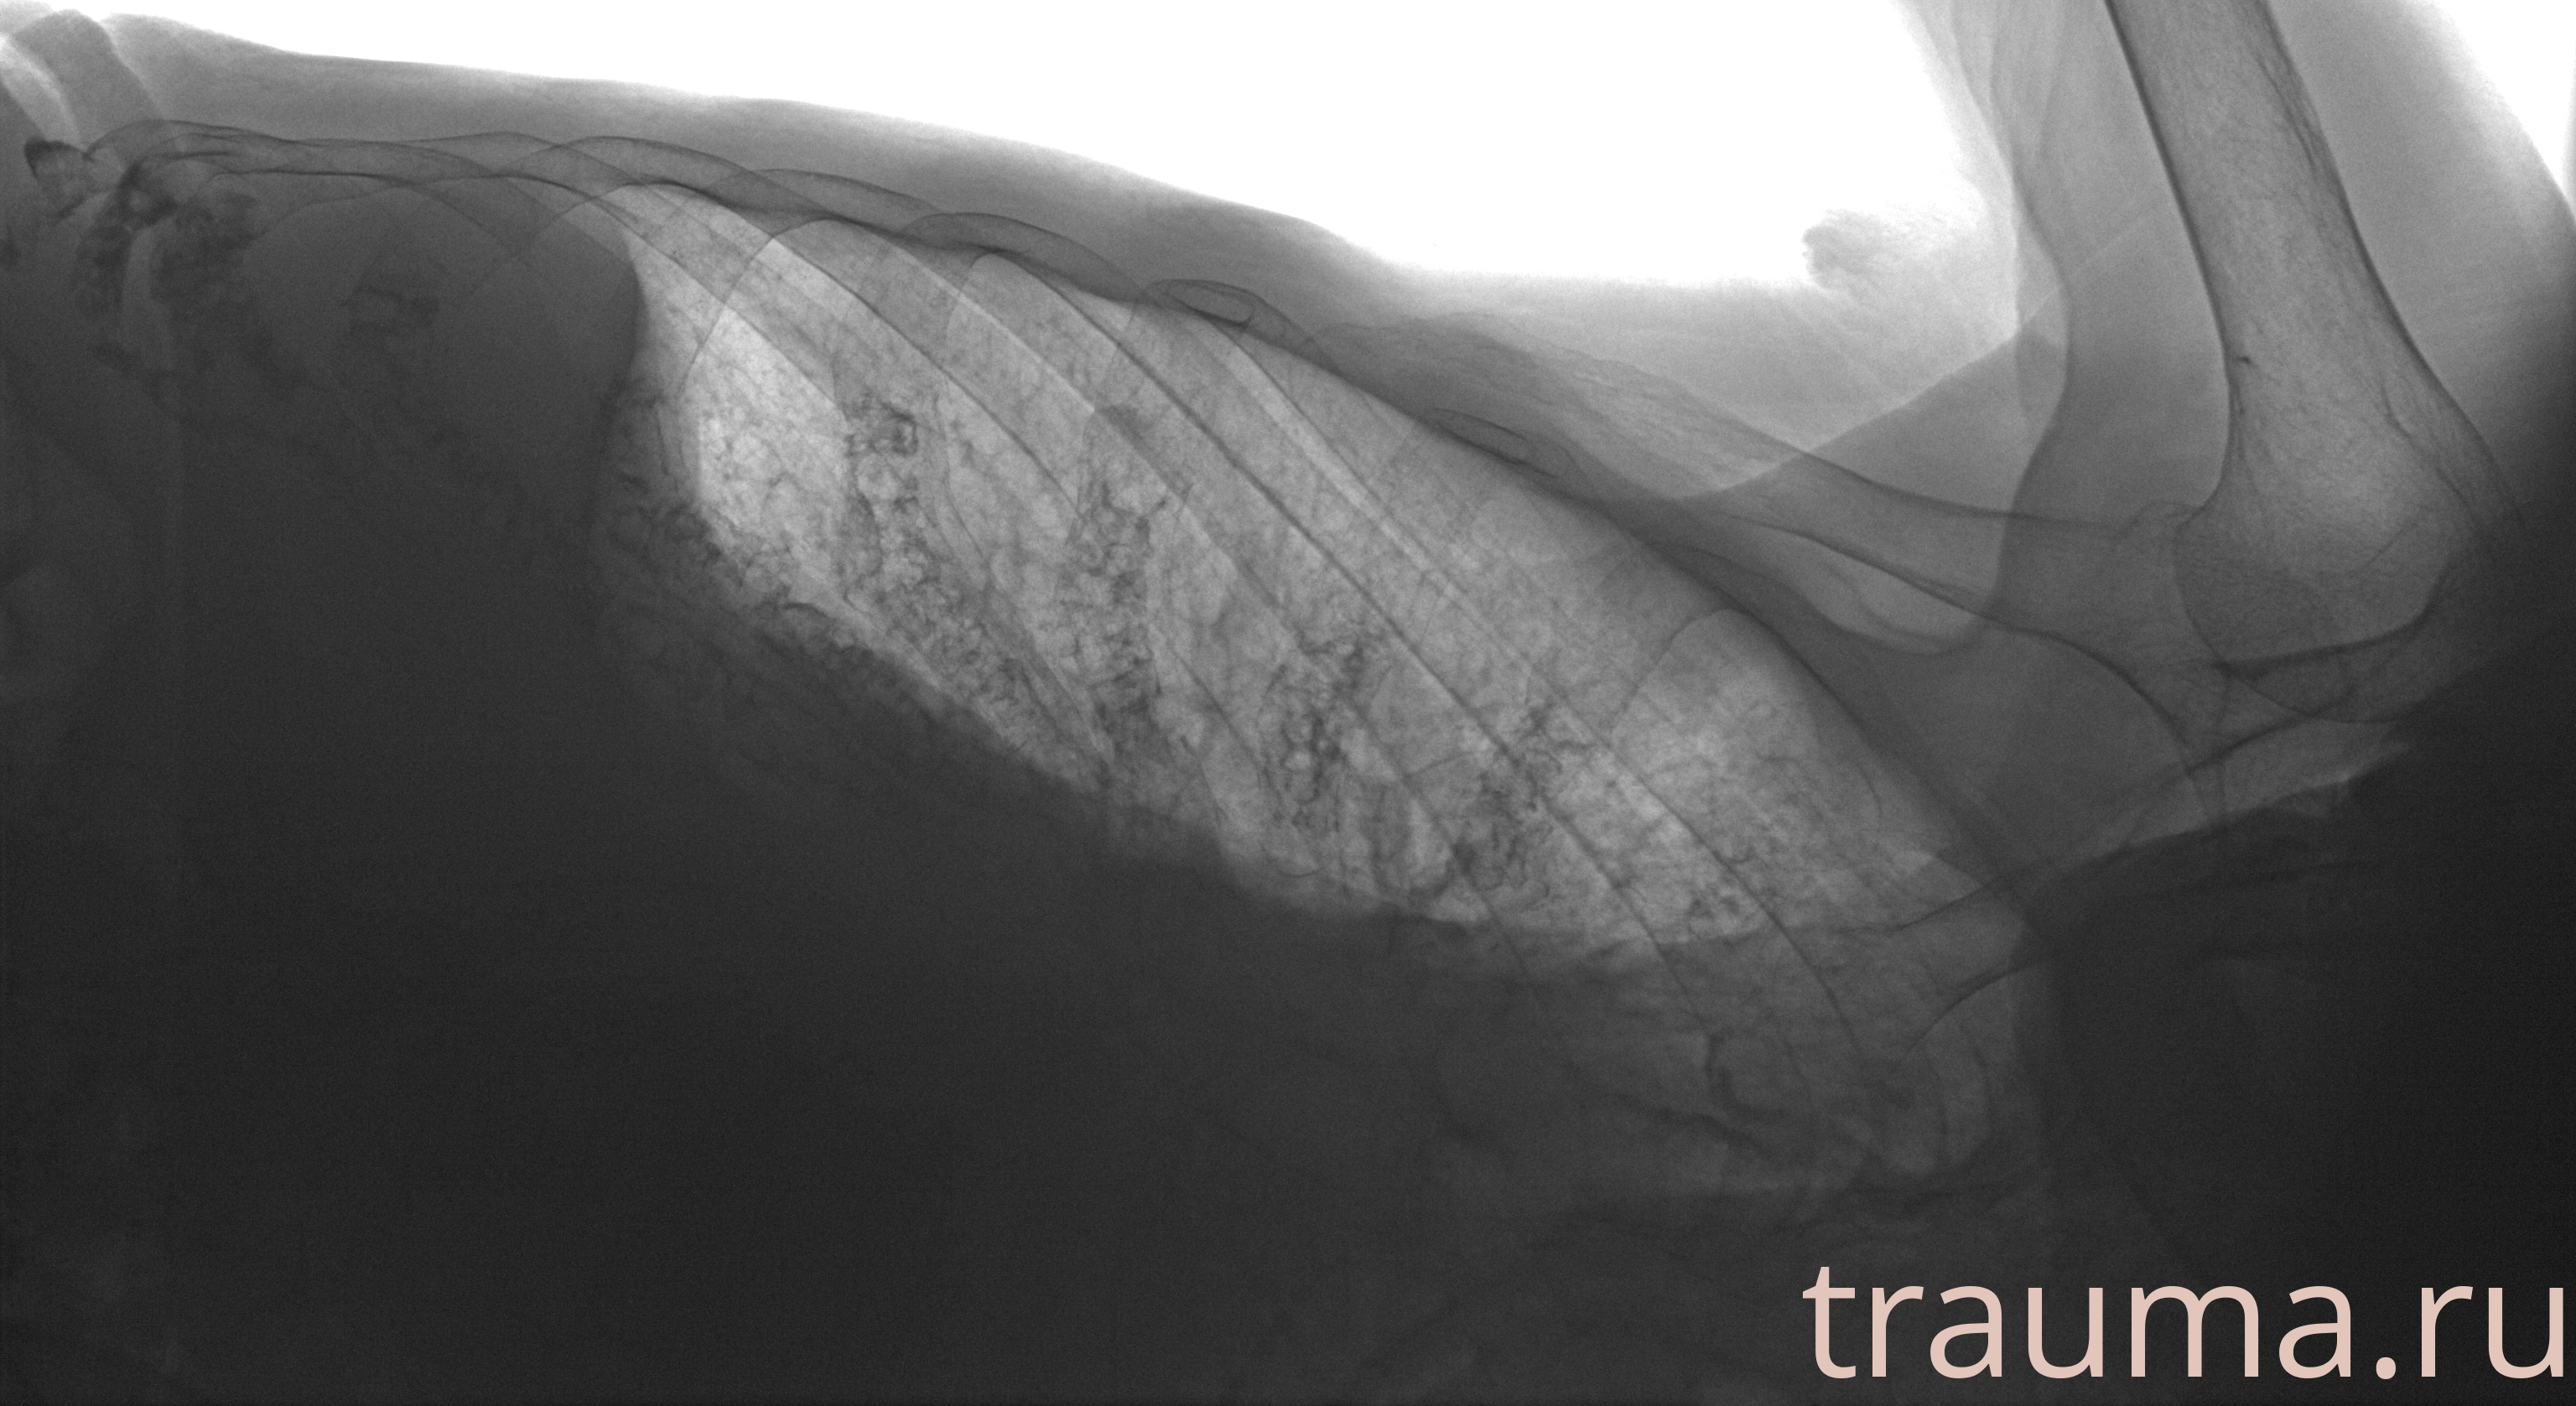

Рентген на дому: по вашему адресу приезжает врач-рентгенолог, травматолог-ортопед с мобильным рентгеновским аппаратом, проводит диагностику травмы или заболевания, делает необходимые рентгенограммы, дает рекомендации по дальнейшему лечению. Получить качественные снимки в домашних условиях возможно благодаря уникальной методике, разработанной МосРентген Центром для института  Склифосовского

при переломе шейки бедра и пневмонии от компании МосРентген Центр - партнера Института имени Склифосовского